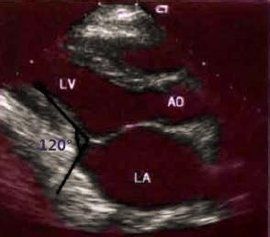

心包叩擊音(pericardial knock):縮窄性心包炎時,可在第二心音後約0.09~0.12s處出現的中頻、較響而短促的額外心音。這是由於心包增厚,在心室快速充盈時,心室舒張受限,被迫驟然停止,使室壁振動產生此聲音。心包叩擊音聽診在心尖部和胸骨下段左緣最清楚。